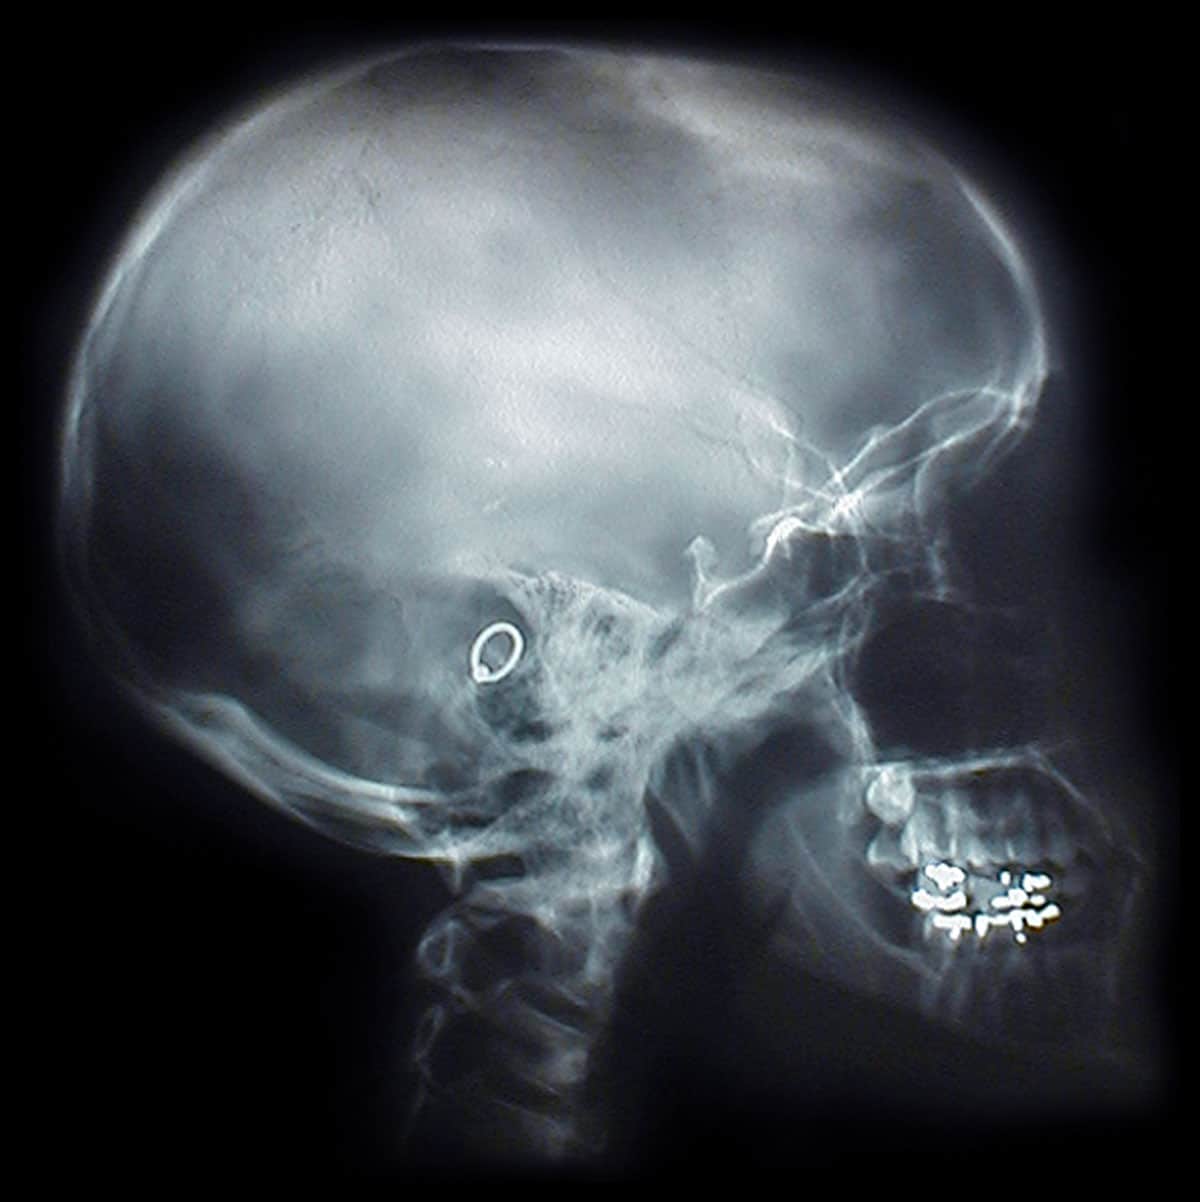

Medical Hacking

Last year the news were flooded with reports of all kinds of big companies getting hacked, along with users being hit with things like ransom ware, the question is what’s next.

This is why health industries are coming under fire and a pretty good reason for technology manufactures to start concentrating on security which is something that’s been lacking for many years now. Yes where there is a will, there is a way and hackers will always be trying to take advantage of that but with the knowledge we have today companies should be constantly developing newer security measures especially on devices like these.